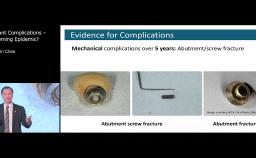

This lecture gives an overview of the relevant comparative anatomy and histology surrounding teeth and implants in healthy or pathologic conditions. Emphasis is placed on creating physiologic relationships and minimizing inflammation. The influence of factors such as the implant-abutment interface, timing of loading, surface characteristics, and the presence of inflammation are discussed based on current evidence.

- discuss the influence of the implant-abutment interface, loading, and surface characteristics on the dimensions and quality of the supracrestal soft tissue attachment around implants